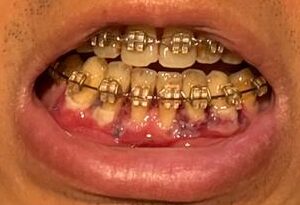

左(上)から:術後5時間後、術後17時間後、術後1週間後、術後3週間後

左(上)から:術後3時間後、術後19時間後、34時間後、58時間後、65時間後、89時間後、114時間後、154時間後

・2026年2月21日撮影

・2025年9月13日撮影

・2022年10月1日撮影(約3年前)